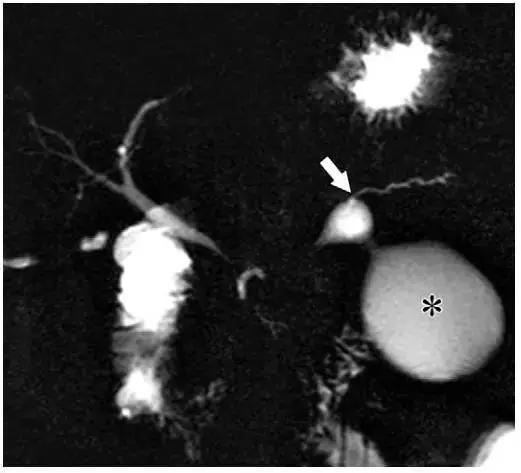

图 7 一名 55 岁伴有胰管分离综合征的假性囊肿女性患者。冠状位 MRCP 示胰周和胰腺内假性囊肿(*)和胰尾部轻度扩张的胰管(箭头)相通。需要注意的是胰尾部胰管因为胰体坏死与壶腹部不相通

在 MR 成像中,假性囊肿表现为均匀高 T2 信号(图 6)。MRCP 具有高组织分辨率,可以显示部分假性囊肿与胰管相通(图 7)。

在这些病例中,坏死组织清除术后或胰体坏死,而胰尾仍有功能,分泌胰液并从胰管内漏出形成假性囊肿(图 7)。